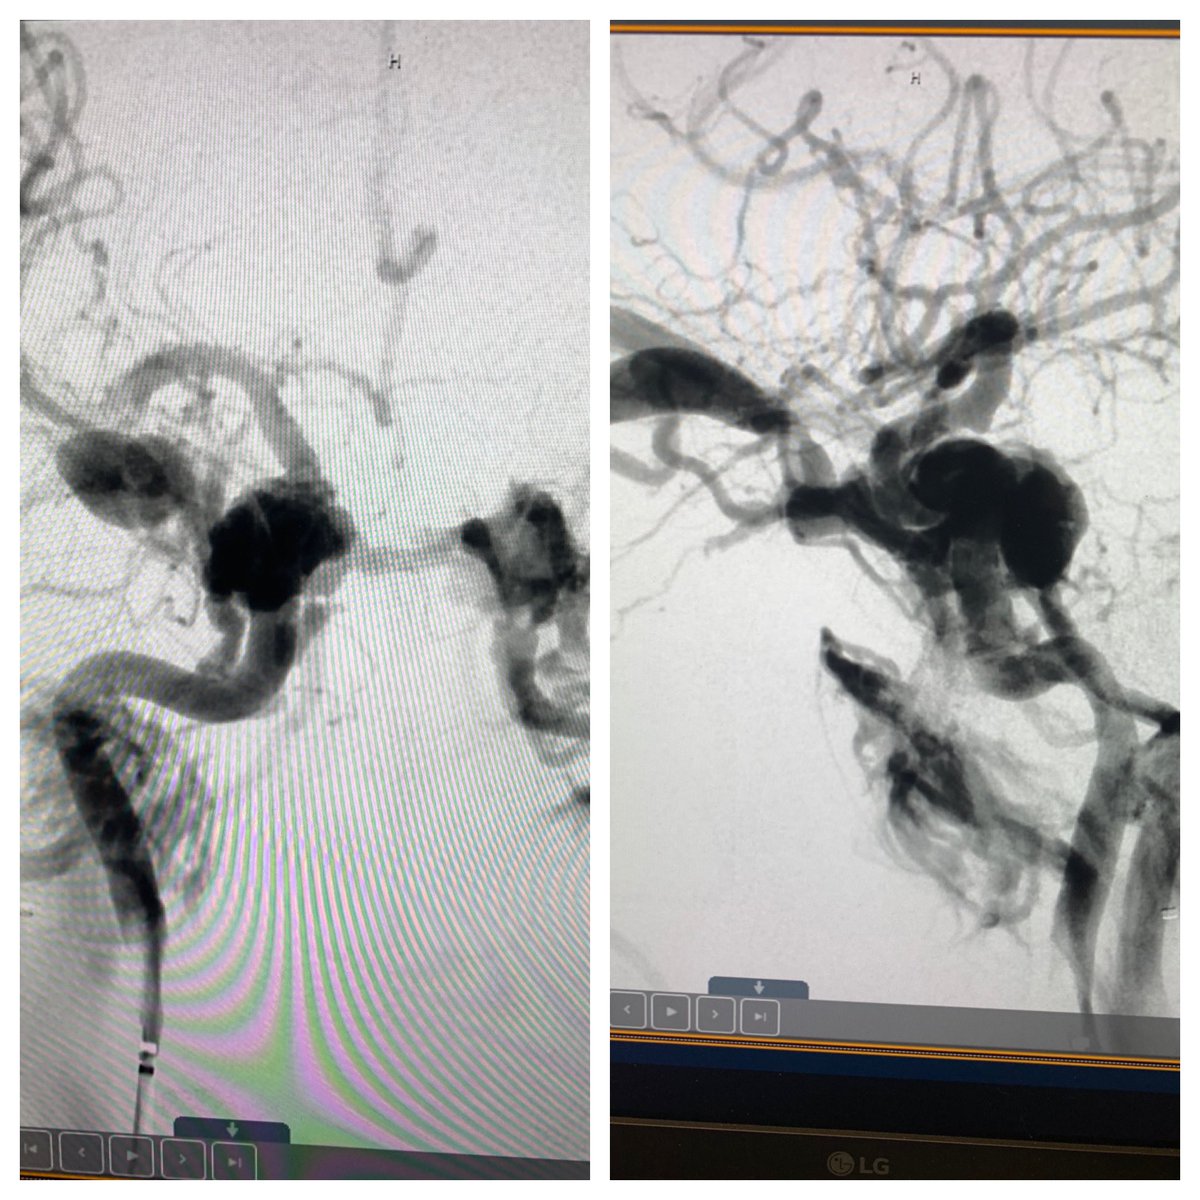

We are so focused on radial ARTERY access, why make venous access more streamlined for patients? Direct CCF a few weeks after MVC Sheaths in distal radial and AC stick into basilic vein Coils in cav sinus transvenous with balloon inflated TRA in ICA

#RadialFirst#RadialforNeuropic.twitter.com/Ydz0KCzjHp